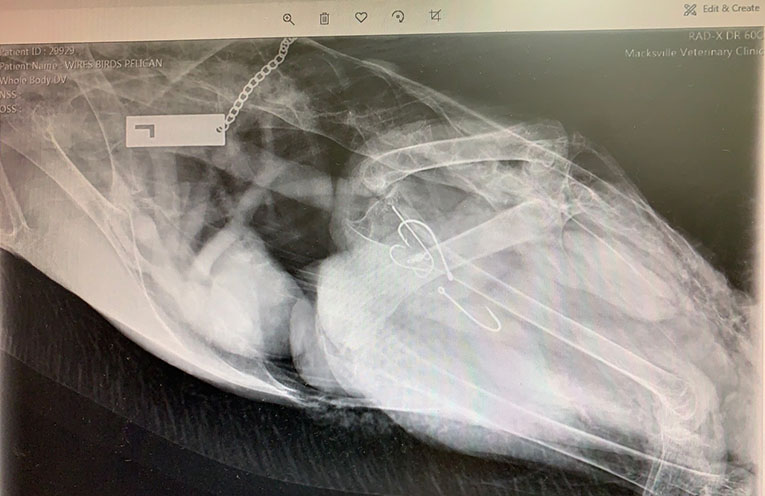

WIRES is pleased to report that three of the rescues were successfully treated by Dr Neale including one pelican with multiple hooks in stomach and after a few weeks in rehabilitation they have been released back into the waterways where they were rescued.